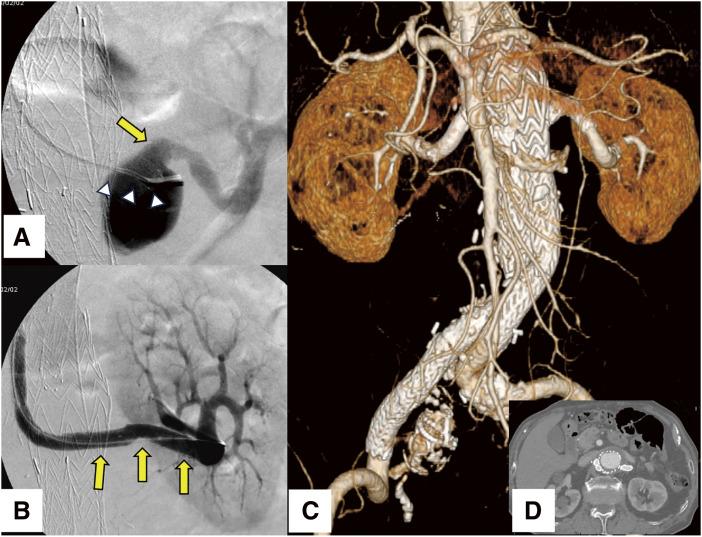

A 78-year-old male presented with progressive enlargement of a pararenal abdominal aortic aneurysm following chimney endovascular aneurysm repair. The aneurysmal expansion was attributed to an endoleak secondary to migration of the left renal artery chimney stent graft, resulting in a 5-mm increase in aneurysm diameter over 6 months. Endovascular reintervention successfully induced aneurysm regression, with no recurrence of endoleak on annual imaging follow-up. While chimney endovascular aneurysm repair presents a minimally invasive alternative for managing complex aortic pathologies, including pararenal abdominal aortic aneurysms, vigilance regarding potential stent graft migration is essential.